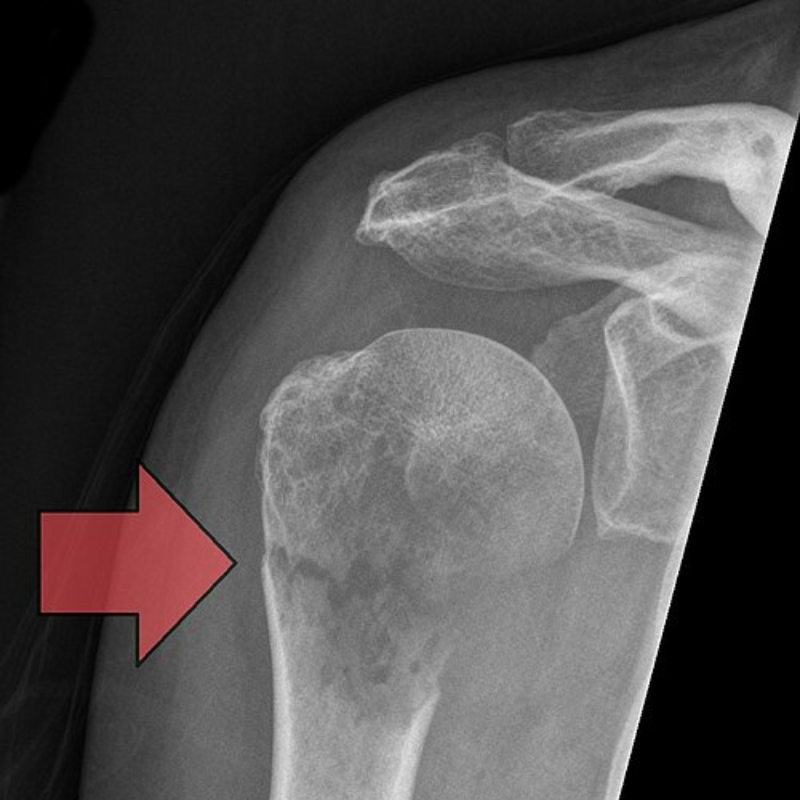

If you fracture your bone from a minor fall or even a bump, it is a big red flag. This is known as a pathological fracture and it is seen in 7-35% of the patients (Digital Commons) with this diagnosis. It occurs when bone cancer weakens the structural integrity of the bone.

People may ask ‘Is a fracture always due to trauma?’ But no, the weakening bone due to the tumor may crack or snap from regular pressure.